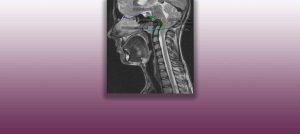

L’Institut Chiari di Barcellona è un centro neurochirurgico di alta specializzazione dedicato alla diagnosi e al trattamento delle malattie della colonna vertebrale e dell’encefalo, focalizzandosi sul concetto clinico della Malattia del Filum Terminale. Tra le patologie trattate vi sono: